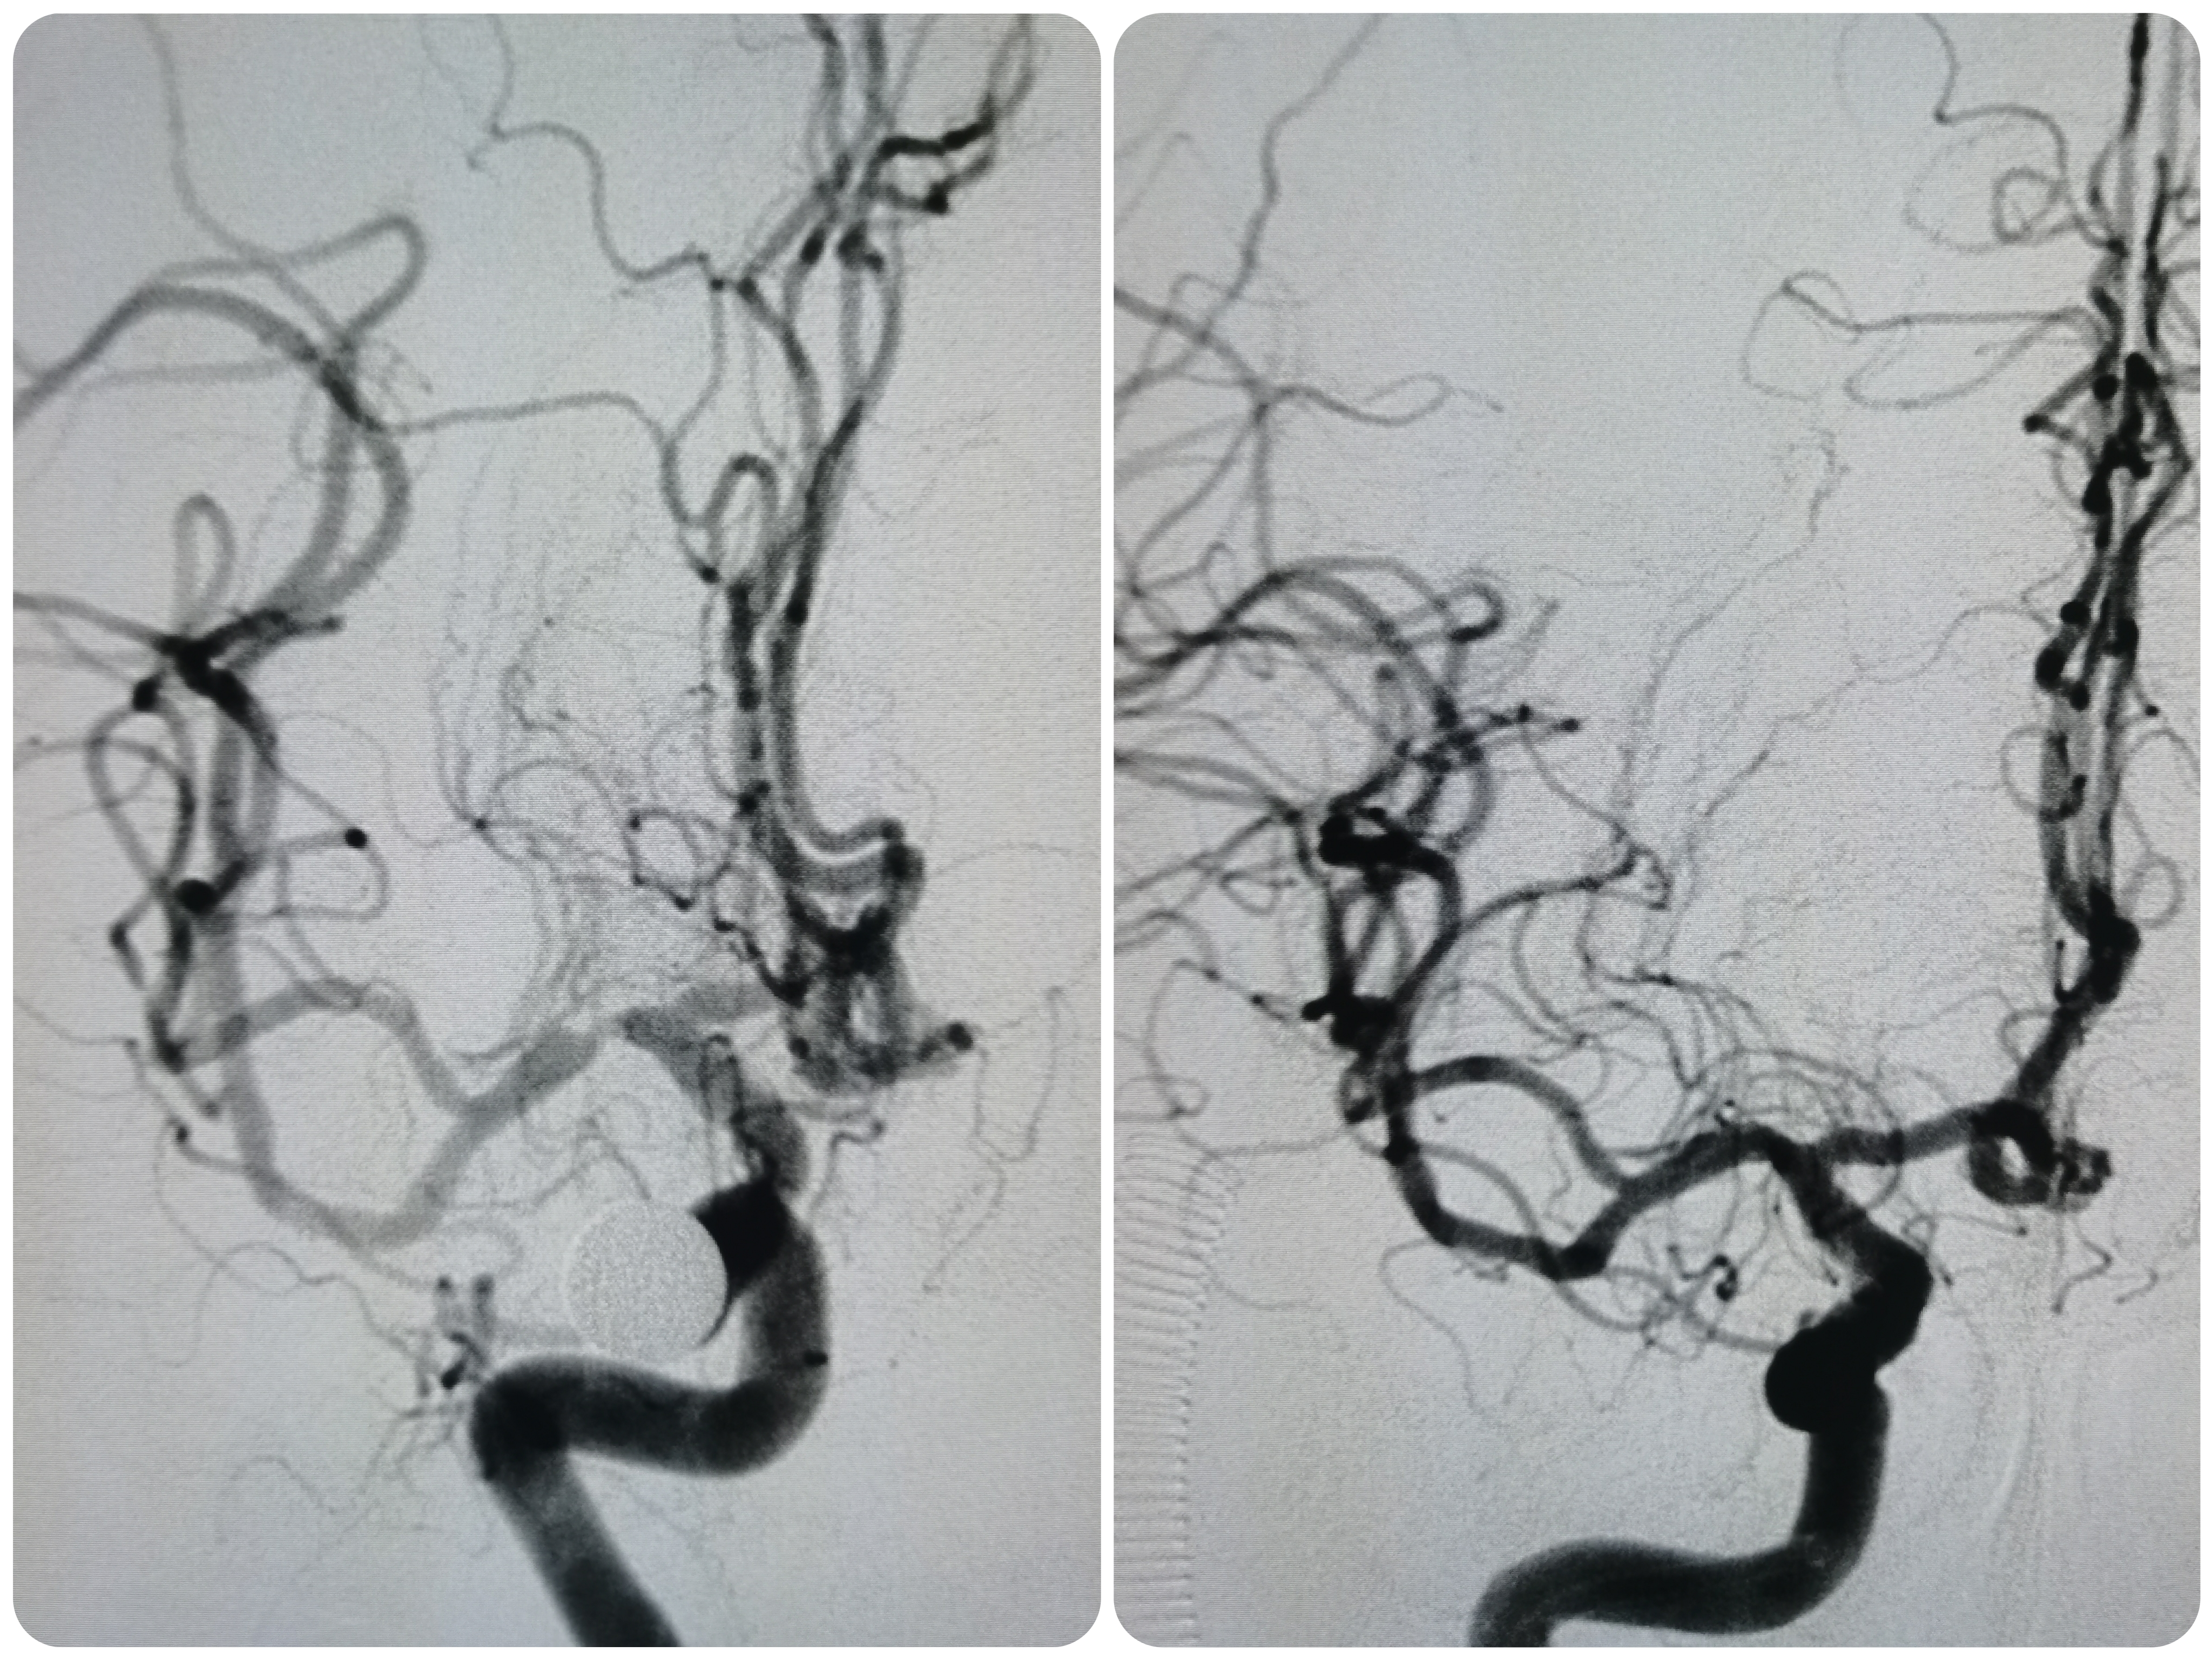

球扩后造影见狭窄解除,豆纹动脉显影良好,远端血供改善,未见夹层征象。

正位造影见狭窄解除,颅内血流通畅。

观察15分钟后造影未见明显弹性回缩。

术前术后对比